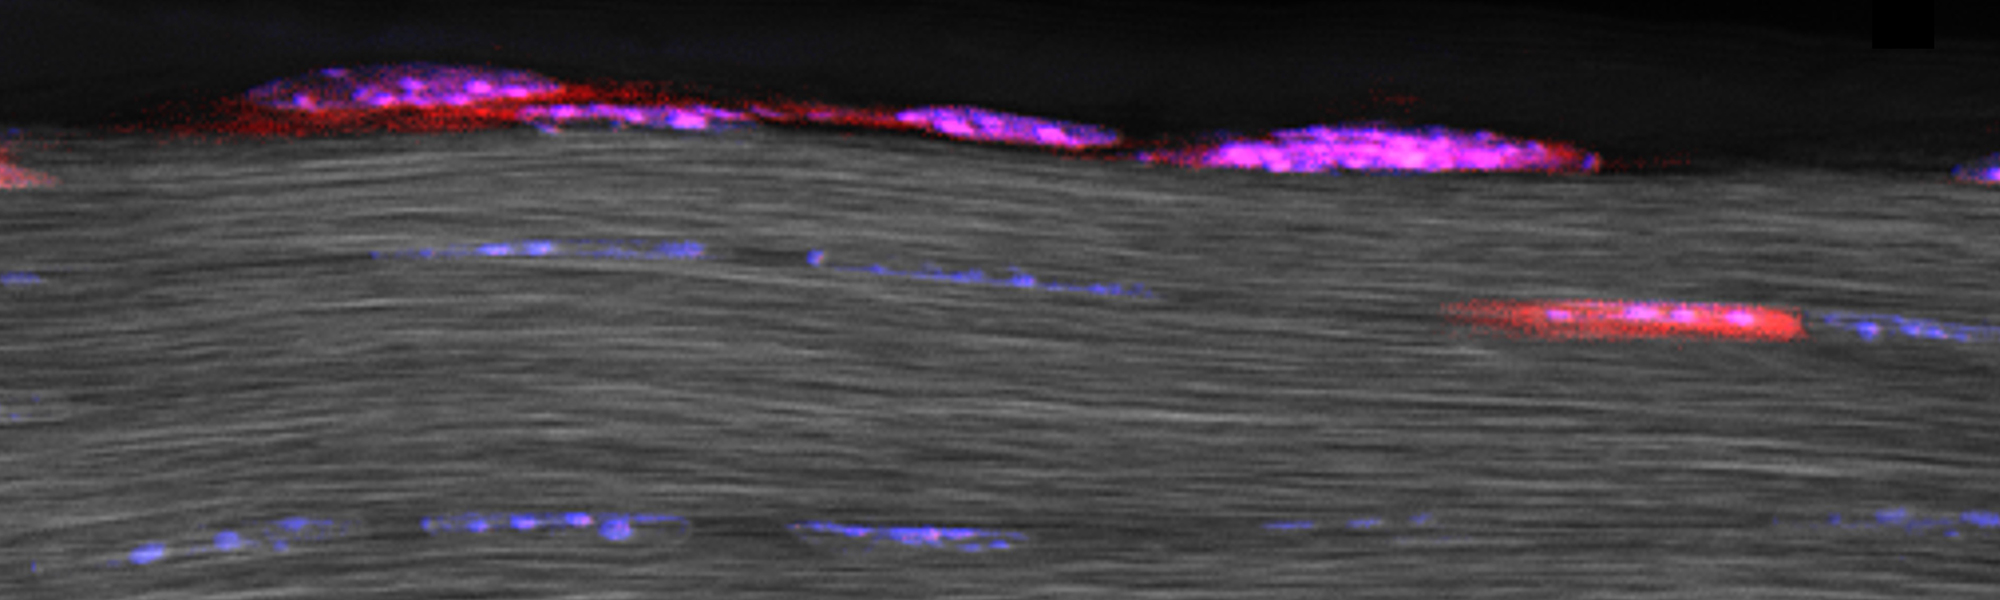

The Identity, Function, and Fate of Epitenon-Derived Progenitor Cells in Tendon Healing

Epitenon-Tenocyte Mechanotransduction in Tendon Homeostasis and Adaptation

The Origins of Pain in Injured Tendons